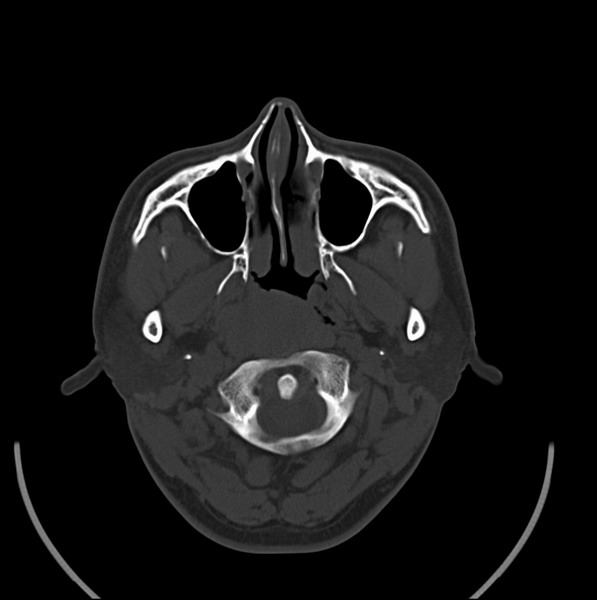

男、30、发现鼻咽部肿瘤侵犯海绵窦,未发现明显淋巴肿。请问国内那家医院治疗鼻咽部肿瘤最好?手术以何种方式为主?病灶可否全部切除?急切期待的大家的帮助。

扫描示鼻咽腔不对称,中度狭窄,右侧咽隐窝消失,局部软组织肿块,鼻咽右侧壁增厚形成肿块,突入鼻咽腔,肿块平扫呈等密度,肿块向深部侵润,右侧翼内外肌受侵,右侧咽旁间隙变窄;向后生长,头长肌界线欠清,向后上生长侵犯同侧颈动脉鞘区。双侧海绵窦增宽,内见软组织影与鼻咽部肿块相连。考虑鼻咽癌。鼻咽癌主要是放射治疗,且效果较好;到当地有治疗设备较大医院治疗即可。